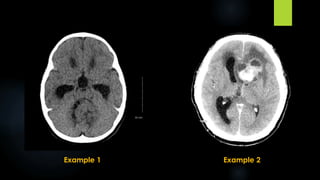

 CT:

 Most are isodense

 50 % cases show calcification

 Overt hemorrhage is uncommon

 Mild to moderate inhomogenous enhancement is

seen in 70 % of cases

Example 1 Example 2